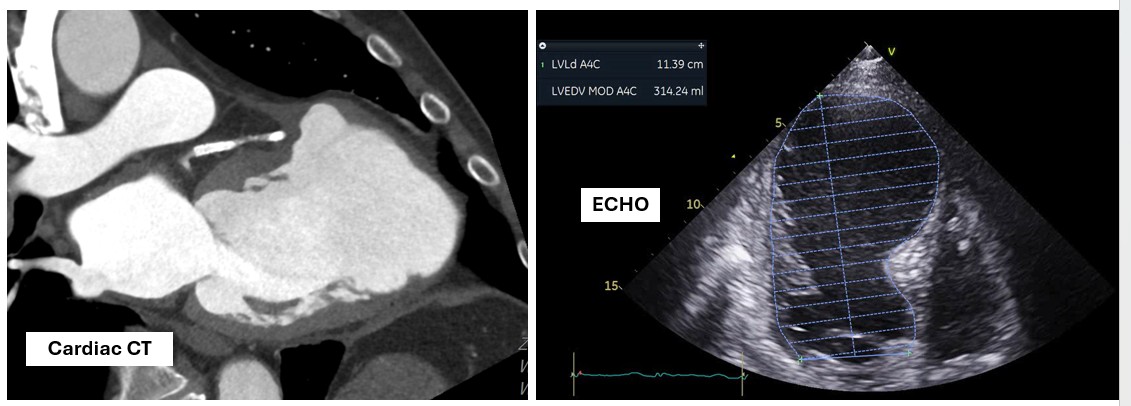

Several investigations were performed to prepare the 67-year-old patient for repeat coronary angiography, with plan for DCB or PCI if required. The team carefully reviewed her clinical stability, cardiac enzymes and imaging results to decide the safest path forward. Each step reflected both urgency and hope to restore her coronary flow and prevent another critical cardiac event from threatening her recovery.

A covered stent was deployed in the distal LAD in an attempt to seal the coronary perforation; however, angiography showed that the Type III perforation persisted despite the intervention. Additional balloon inflation within the stent was performed, but the leakage could not be completely sealed. The patient remained hemodynamically stable without signs of cardiac tamponade or pericardial effusion. The following day, repeat coronary angiography was conducted to reassess the condition, which confirmed persistent contrast extravasation from the LAD into the left ventricular cavity, indicating the formation of a coronary–ventricular fistula. Given the hemodynamic significance and the risk of progressive left ventricular dysfunction due to continuous shunting, a multidisciplinary decision was made to proceed with surgical correction. The patient subsequently underwent successful LAD–LV fistula patch repair combined with. Surgical repair remains the definitive management for such cases, and early recognition with timely intervention is crucial to restore cardiac function and prevent irreversible myocardial damage.

The patient underwent successful surgical patch closure of the LAD–LV fistula along with ventricular reconstruction to restore myocardial integrity. The postoperative recovery was smooth and uneventful, with stable hemodynamics throughout hospitalization. Follow-up echocardiography demonstrated significant improvement in LVEF to 53%, and she remained asymptomatic during subsequent outpatient follow-up